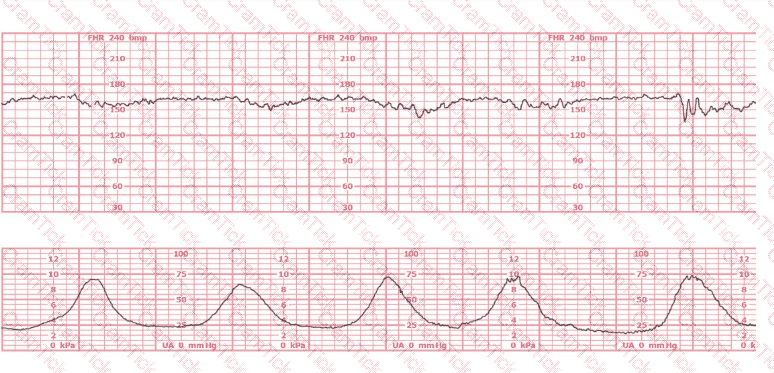

This is a fetal heart rate tracing of a multiparous woman whose cervix is 7 cm dilated on admission. The most likely cause for this pattern is: